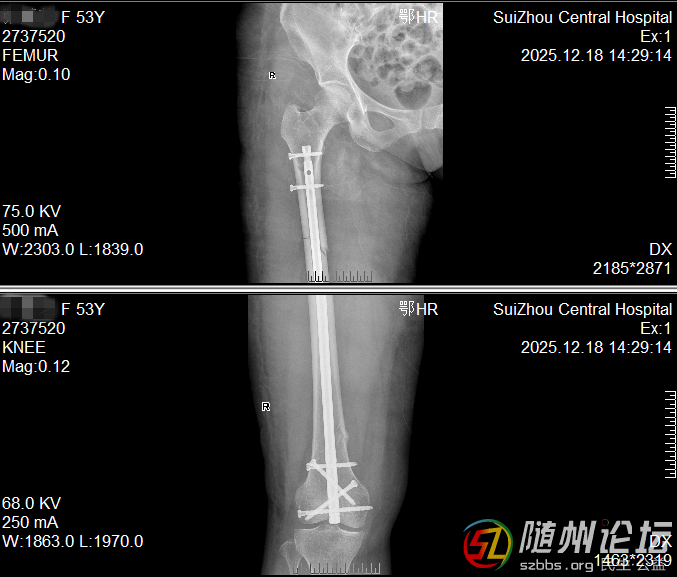

大腿多段骨折,一個(gè)小口完成修復(fù)

一位53女士大腿多處骨折,甚至影響到膝蓋。我們僅在膝蓋上方開一個(gè)約4厘米的小口,放入一根髓內(nèi)釘將骨折處全部連接固定。這樣既保護(hù)了腿部血流和肌肉,也為后期膝蓋活動(dòng)打下了好基礎(chǔ)。